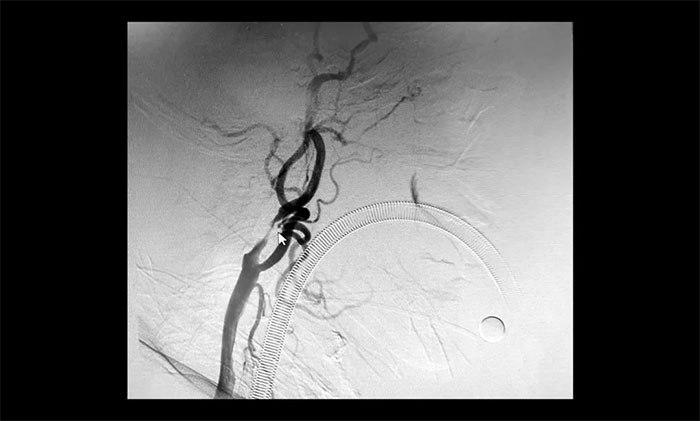

在明确告知分期手术方案,并取得患者家属同意后,5月21日,于耀宇主任和团队医生在全麻下为曹老伯先行脑血管造影术+左侧颈内动脉支架经皮置入术,术后给予预防感染、护胃、补液等对症治疗。

▲ 术后,左侧颈内动脉狭窄明显改善